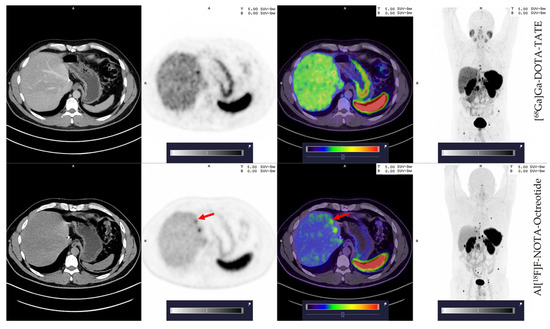

3.2. Tumoral Lesion Detection of [68Ga]Ga-DOTA-TATE Compared to Al[18F]F-NOTA-Octreotide